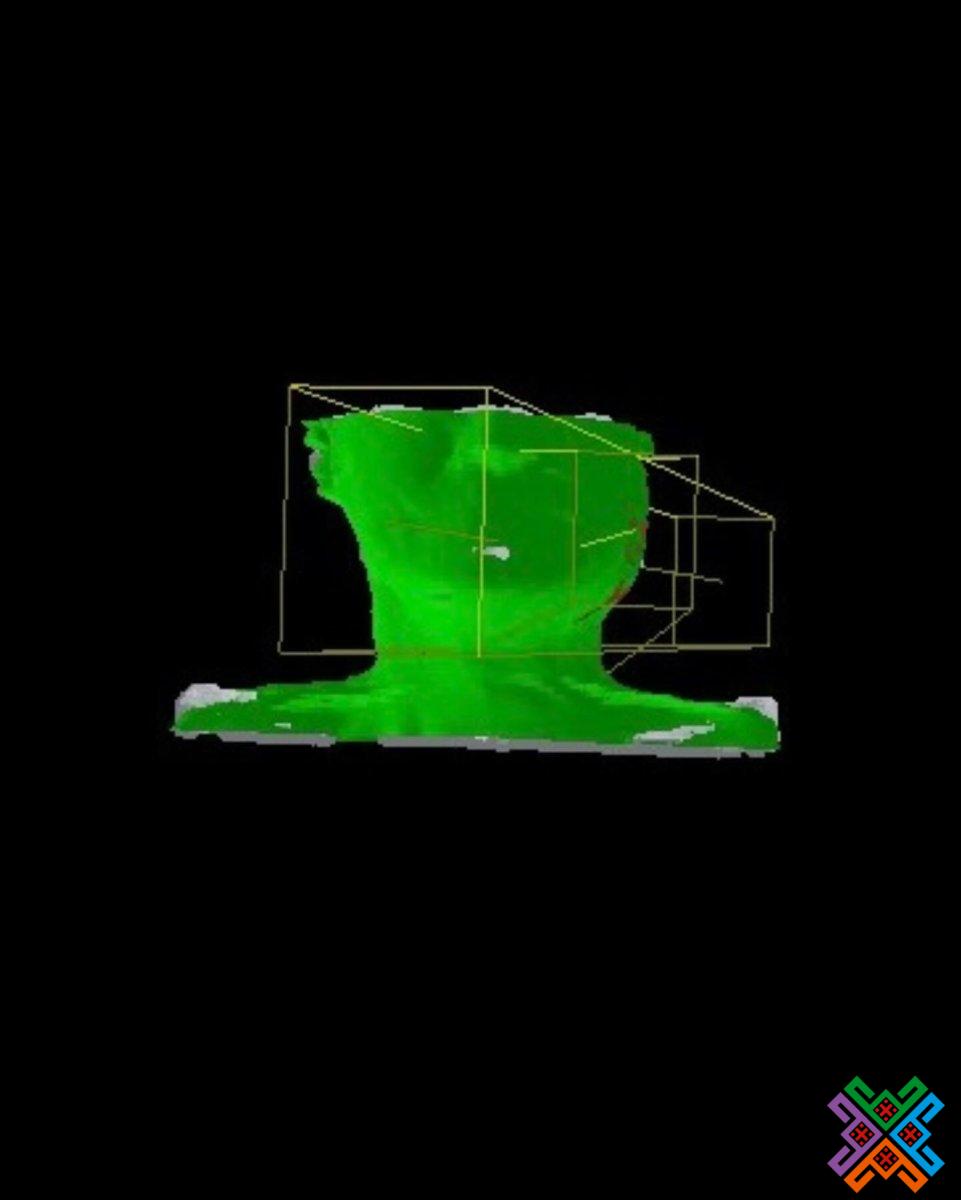

- Проводять топометричну підготовку, аби розрахувати потрібну дозу й час опромінення.

- Застосовують КТ-топометрію, щоб перенести розрахунки з плану на тіло пацієнта якнайточніше.

- мінімальний вплив на здорові тканини;

- максимальна ефективність;